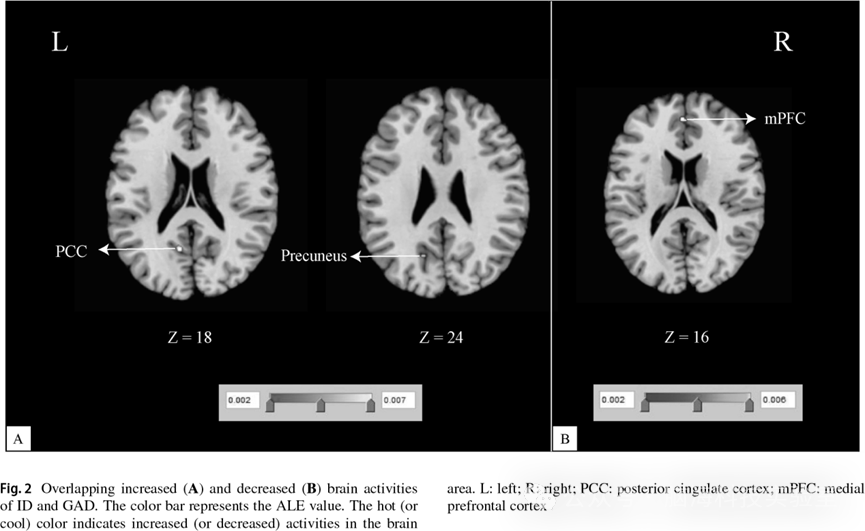

图2 二级分析结果;重叠的脑活动增强区域(图 2A);重叠的脑活动降低区域(图 2B)

ID > HC 与 GAD > HC 的联合分析结果显示,左侧后扣带回(posterior cingulate cortex,PCC)和左侧楔前叶(precuneus)为两种障碍中共同表现出脑活动增强的脑区(见表 3、图 2A)。ID < HC 与 GAD < HC 的联合分析结果表明,两种障碍中共同表现出脑活动降低的脑区位于左侧内侧前额叶皮层(medial prefrontal cortex,mPFC)(见表 3、图 2B)。